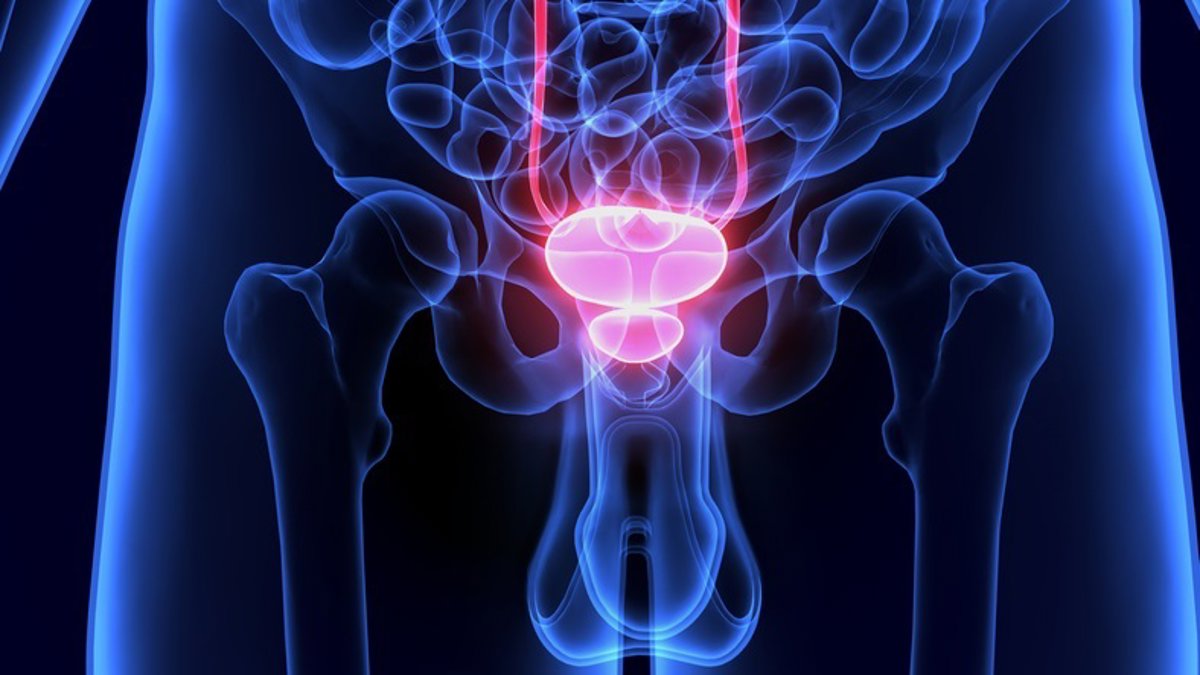

Los **avances terapéuticos** y el **diagnóstico molecular** han logrado triplicar en 15 años la supervivencia de los pacientes con **cáncer de próstata avanzado**, que representan el 10 por ciento de los casos diagnosticados de este tipo de tumor, mientras que la mayoría se detectan en estadios iniciales.

La **Sociedad Española de Oncología Médica (SEOM)** ha destacado progresos como la combinación de **inhibidores de PARP** con tratamientos hormonales o el radiofármaco **177Lu-PSMA-617**, que ha fortalecido el papel de la terapia dirigida al antígeno de membrana específico de la próstata (PSMA) como un pilar «fundamental» en el manejo del cáncer de próstata avanzado, con motivo del **Día Mundial del Cáncer de Próstata**, que se conmemora este miércoles.

Las innovaciones continuas a lo largo de los años, especialmente en estadios avanzados, han permitido aumentar la mediana de supervivencia de 18 meses en 2005 a más de 40 meses en la actualidad.

En el caso del **cáncer de próstata hormonosensible metastásico**, los tratamientos incluyen combinaciones de agentes hormonales como **apalutamida**, **enzalutamida**, **abiraterona** o **darolutamida**, o tripletes que asocian **docetaxel** con agentes hormonales como abiraterona o darolutamida.

Para la enfermedad resistente a **castración**, las opciones se amplían a quimioterapia con docetaxel o cabazitaxel, nuevos agentes hormonales como abiraterona o enzalutamida, y radiofármacos como **radio-223** o **177Lu-PSMA-617**, seleccionándose según las características del paciente y los tratamientos previos.

El reciente estudio **Peace-3** ha demostrado que la combinación de **enzalutamida** con **radio-223** mejora la supervivencia de pacientes con cáncer de próstata resistente a la castración metastásico con enfermedad ósea (CPRCm), reafirmando el valor de las terapias dirigidas al hueso.

Durante los últimos años, los **inhibidores de PARP** también han mostrado eficacia en CPRCm, y estudios como **Amplitude** han concluido beneficios de esta estrategia en etapas más tempranas de la enfermedad.

En cualquier caso, los objetivos de tratamiento para estos dos subtipos son prolongar la supervivencia del paciente, preservar la calidad de vida y prevenir eventos óseos.

Para pacientes con carcinoma de próstata resistente a la castración que aún no han desarrollado metástasis, se han introducido tratamientos basados en **apalutamida** como enzalutamida y darolutamida, demostrando un retraso en la aparición de metástasis y un aumento de la supervivencia global.

Por otro lado, la SEOM ha resaltado que uno de los desafíos más importantes de la actualidad es definir la **secuencia óptima de fármacos**, para lograr el máximo beneficio en cada paciente de manera personalizada.

Los continuos avances en investigación también han beneficiado a los diagnósticos, incorporando la **tomografía por emisión de positrones con PSMA**, que proporciona mayor sensibilidad y especificidad. Para más detalles sobre diagnóstico molecular, visita esta página.

Además, se ha incluido en las guías clínicas la recomendación de realizar un análisis rutinario de genes relacionados con la reparación homóloga (como **BRCA1/2**), tanto para seleccionar pacientes candidatos a **inhibidores de PARP** como para asesoramiento familiar. Infórmate más sobre tratamientos genéticos en esta fuente.